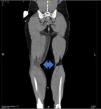

Varón con shock séptico de partes blandas por Streptococcus pyogenes tras traumatismo. Diseminación hematógena con fascitis necrosante en extremidades (resección quirúrgica) y meningitis con absceso cerebral (craniectomía y evacuación). Tomografía (TAC) con contraste: edema en el tejido subcutáneo del brazo izquierdo y en los vientres musculares, y colección en la cara medial de la pierna derecha (fig. 1, flecha azul). Hematoma craneal lobar parietooccipital derecho, edema vasogénico y hemorragia subaracnoidea traumática en cisternas, con aumento del efecto masa (borramiento de surcos y compresión del ventrículo lateral derecho) (fig. 2, recuadro naranja). Resonancia craneal tras empeoramiento clínico (fig. 3): colección occipitotemporal derecha de 3,5×9cm, márgenes irregulares hipercaptantes y restricción (estrellas rojas) sugestiva de absceso cerebral, con pus intraventricular, herniación subfalciana y uncal derecha (flechas rojas), así como hematoma subdural a nivel de la craniectomía (triángulo rojo).